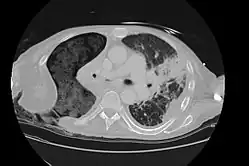

The Eloesser flap is a surgical procedure developed by Dr. Leo Eloesser in 1935 at the San Francisco General Hospital.[1] It was originally intended to aid with drainage of tuberculous empyemas, since at the time there were no effective medications to treat tuberculosis. The procedure was used extensively[2] until the development of effective antimicrobial therapy for tuberculosis in the late 1940s and early 1950s.[3] It is still used occasionally for chronic empyemas.[4][5]

As originally described by Dr. Eloesser, the procedure started with cutting a 2 inch wide, U-shaped flap of skin on the side of the chest wall underneath the axilla and scapula. The section of rib under the top of the flap was also removed. The finger-like skin flap was then inserted into the cavity made in the chest wall and sewn into the inner pleural lining of the chest. The edges of the incision are then brought together.[1] The flap allows for 1) passive drainage of the pleural space and 2) negative pressure to develop in the thoracic cavity due to it being easier for air to escape than to enter the chest. The lung can then expand to the chest wall and seal the inner opening of the flap.[3] Other surgeons have subsequently proposed modifications to the procedure.[6]

The Eloesser flap is still utilized for patients with chronic empyemas who have not improved despite being treated with antibiotics and first line surgical procedures to remove pus and re-expand the lung such as decortication or video-assisted thoracoscopic surgery.[4] Often they are thought to be too ill for more definitive procedures such as a major thoracotomy or muscle flap transposition.[5] In a recent case series, the most common reasons to need an Eloesser flap were parapneumonic effusions and postresection empyemas, with only 9% done for tuberculosis.[4]